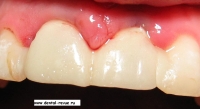

3. Вид до операции.